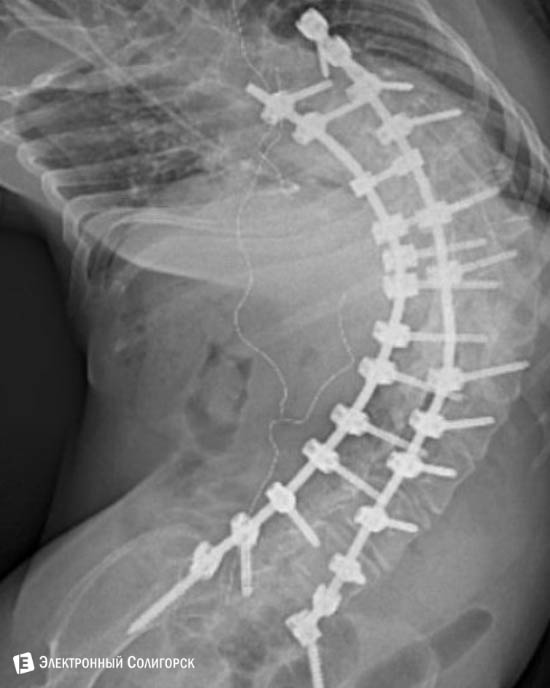

Год назад с помощью неравнодушных людей, родственников и особенно младшей сестры Марины Елена собрала деньги на операцию. Доктор Попов из израильской клиники "Шаарей Цедек" вмонтировал в её позвоночник 2 титановых штифта и 27 винтов.

Позвоночник выровняли на 25 градусов в прямой проекции и на 20 градусов в боковой и жёстко зафиксировали.